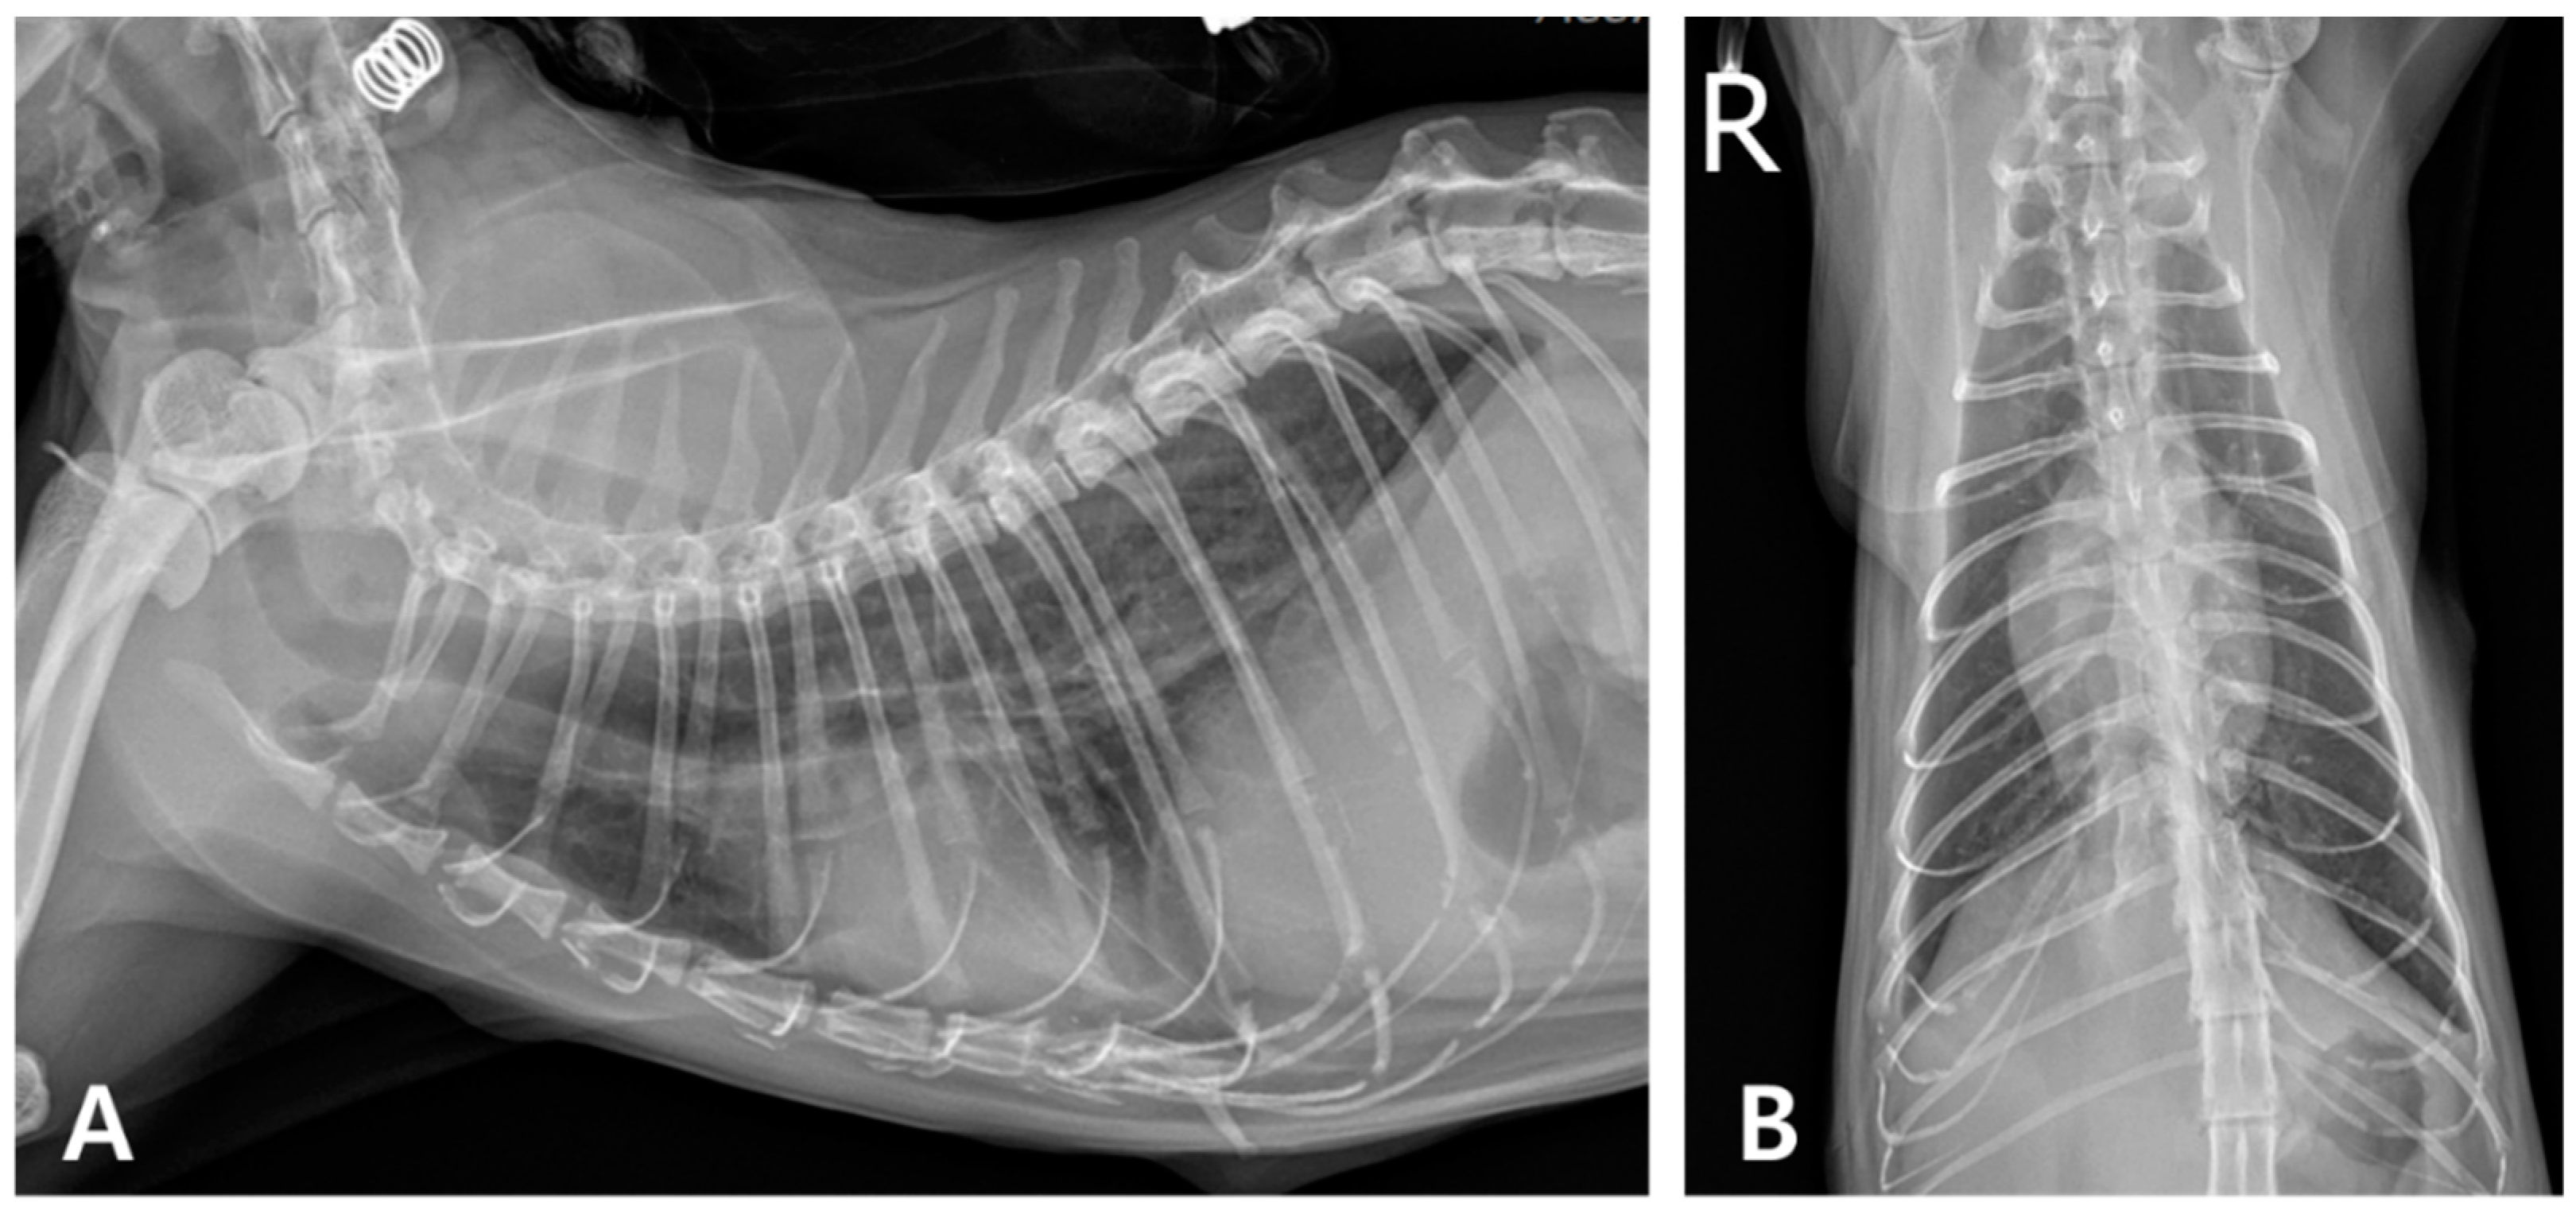

2. Case Description